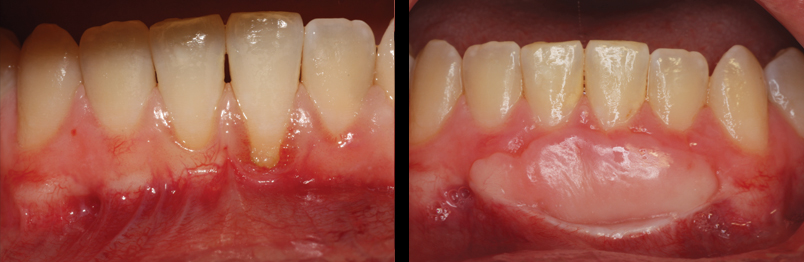

Gingival Graft:

The conventional treatment for recession is the Gingival Graft. The procedure is designed to enhance and reinforce thinning tissue with more durable or …”beefy” gingiva.

Connective Tissue Grafts:

In certain situations, gingival recession can cause a cosmetic problem. The procedure of choice for cases like this is the Connective Tissue Graft. This procedure not only “beefs up” the supporting tissues around a tooth but has the added benefit of cosmetic root coverage.